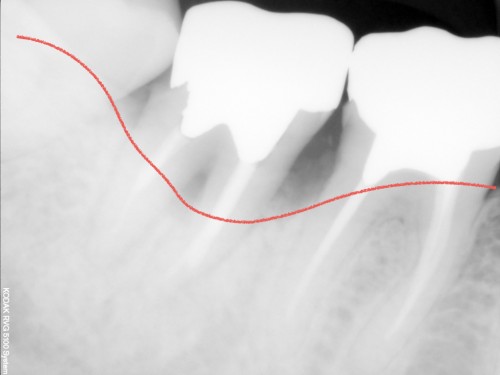

レントゲン写真ですが歯周病の重度の進行があります。

レントゲン写真です。

噛み合わせもしっかり安定しています。